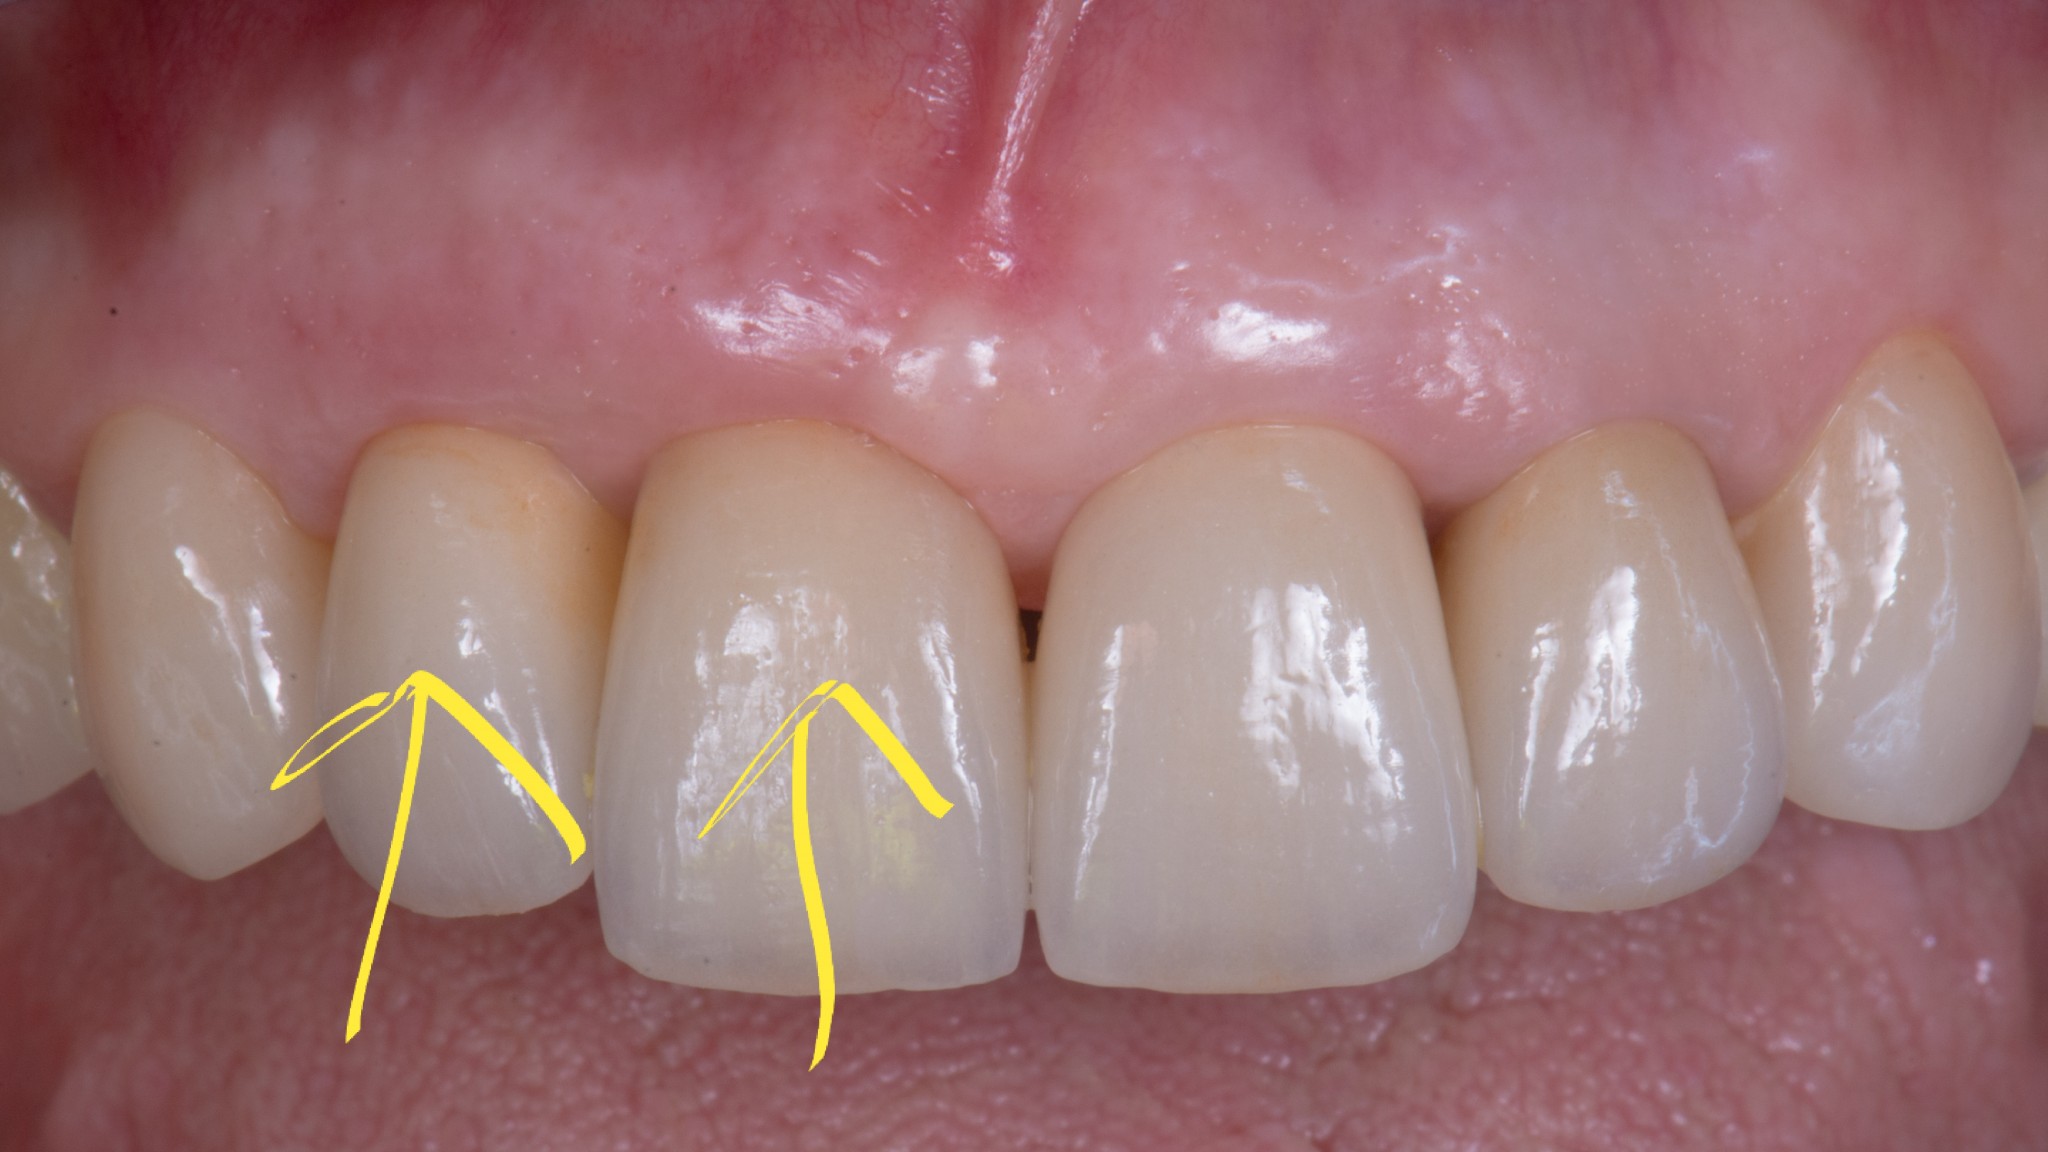

Un dente su impianto oggi ha la possibilità di avere questo aspetto

O questo, se vuoi un esempio frontale.

Soprattutto se si parte da una condizione tissutale ottimale.